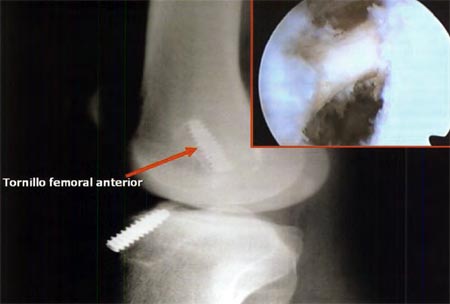

En cuanto a las causas técnicas, lamás frecuente que ocurrió en 20 de los 24 pacientes (83 %), se relacionó con la posición anterior del hoyo femoral, lo cual pudimos ver y suponer radiográficamente y certificar durante la cirugía de revisión, al observar el remanente de una pared posterior de entre 5 a 6 mm, cuando lo que consideramos normal es de 1 a 2 mm. (Fig. 2), mientras que en 2 de los pacientes, la falla tecnica se debió a la posición demasiado posterior del hoyo femoral, con la consecuente ruptura de la pared posterior, hecho que pasó inadvertido durante la cirugía y que posteriormente fue constatado mediante el control radiográfico, visualizándose el tornillo por fuera del cóndilo femoral. (Fig.3)

Figura 2: Posición anterior del hoyo femoral.